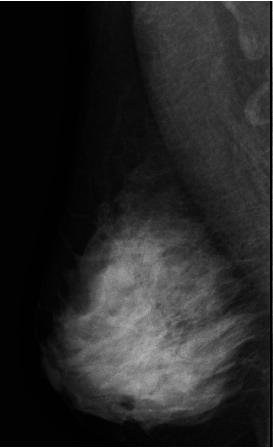

유방암 검사 비용은 보통 유방촬영(영산 진단)과 유방초음파(초음파 진료) 두 가지입니다.

검사할 때 건강보험 혜택이 적용되는 기준은 따로 있습니다. 우선 가장 보편적으로 사용하는 흑백 영상 초음파 장비는 건강보험이 적용됩니다. 단, 진단 결과에 따라서 양성이냐 악성이냐 여부에 따라 최종 결정됩니다.